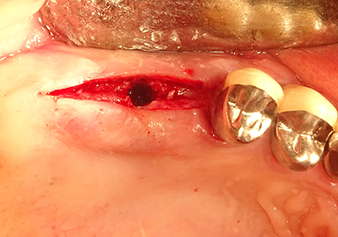

49-летняя пациентка, некурящая и не имеющая ничего примечательного в общей истории болезни, была направлена в нашу хирургическую стоматологическую клинику для хирургического удаления зуба 16 и последующей имплантации. После удаления зуба пациентка перенесла синусит в легкой форме, в результате чего мы сначала выждали шесть месяцев перед проведением операции. Остаточная высота кости при запланированном положении имплантата составляла 3-4 мм (рис. 1 и 2).

Рис.1: Предоперационные данные: Альвеолярный гребень хорошо зажил, включая достаточно широкую, кератинизированную десну.